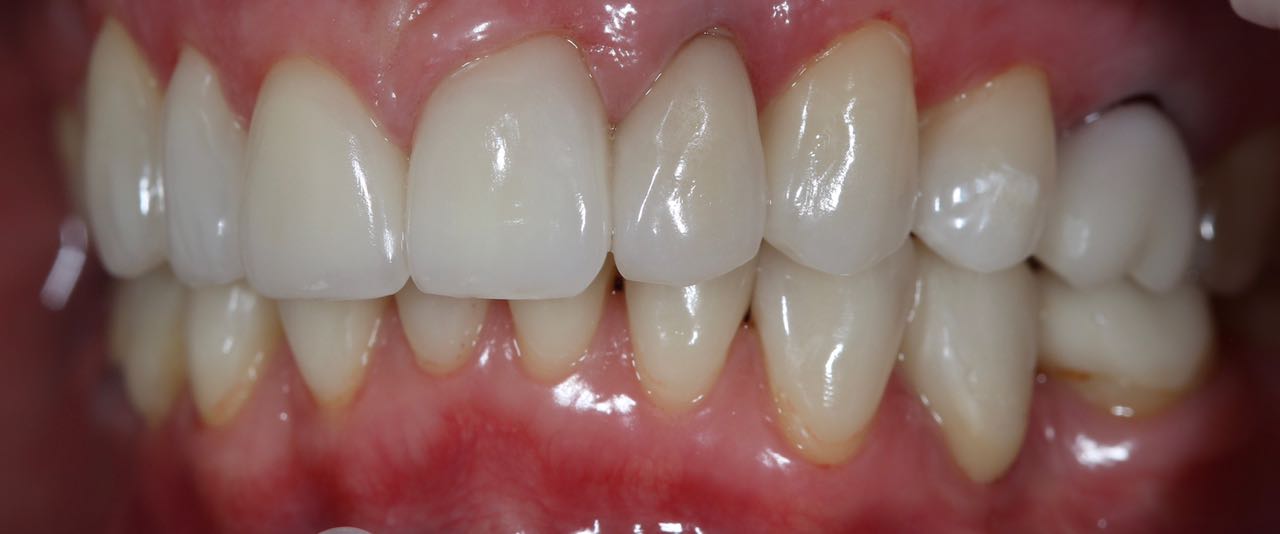

Снова виниры

Замена старых виниров темного цвета на более светлые по причине оголения шейки зуба.

Виниры цвета BLEACH

Установлены керамические виниры на верхнюю челюсть по эстетическим требованиям.